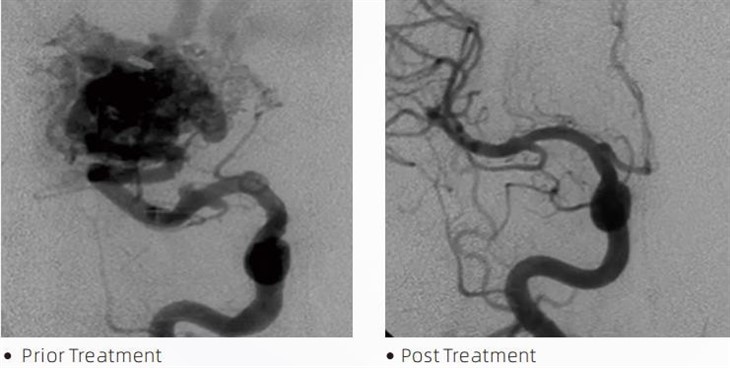

LavaTMembolično lepilo je medicinski pripomoček, ki ga uporabljajo interventni nevroradiologi med minimalno invazivnimi postopki za zdravljenje stanj, kot so možganske anevrizme, arteriovenske malformacije in tumorji. Lepilo Lava embolic ponuja več prednosti tako zdravstvenim delavcem kot bolnikom v smislu varnosti, enostavne uporabe in učinkovitosti. Lava lahko hitro in učinkovito zapre krvne žile. Postopek vključuje vbrizgavanje lepila neposredno v ciljno žilo, kjer se polimerizira in strdi v ulitku podobno maso, ki zapolni anevrizmo ali malformacijo. Nato učinkovito prekine dotok krvi v lezijo, prepreči njeno razpokanje in zmanjša tveganje trajne poškodbe ali možganske kapi. Lava vključuje Lava-12, Lava-18 in Lava-34. Vsaka formulacija je zasnovana tako, da ustreza posebnim kliničnim potrebam. Lava-18 je standardna formulacija za splošno uporabo. Lava-34 je visoko viskozno lepilo za posode z visokim pretokom. Medtem ko ima lava-12 nižjo viskoznost in je bolj pretočna, kar omogoča distalne mikrožile. S temi možnostmi lahko interventni nevroradiologi izberejo ustrezne formulacije Lava za zagotovitev optimalnih rezultatov. Ena najbolj izjemnih lastnosti Lava je njegova nelepljivost. Ta snov je posebej oblikovana tako, da ostane stabilna, dokler ne doseže ciljnega območja. Ta značilnost pomeni, da se lepilo Lava embolic lahko natančno namesti v arterijo in tam ostane, ne da bi se zlepilo ali vezalo na okoliško tkivo.